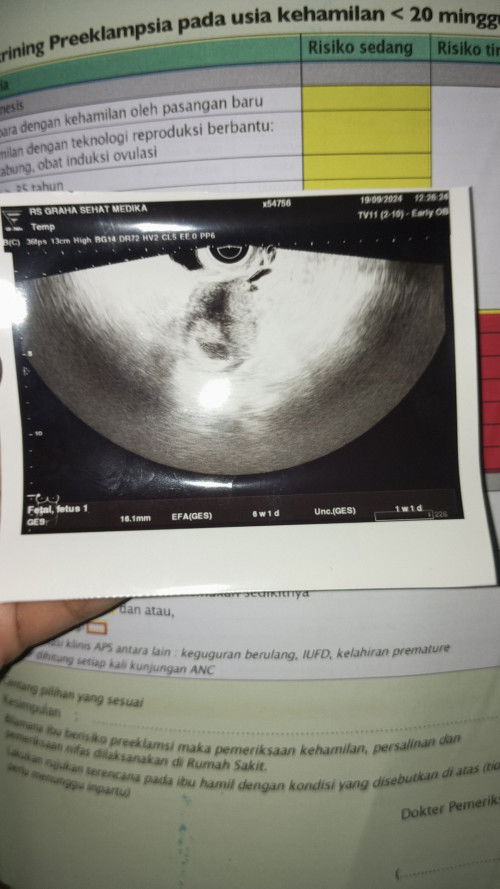

Risau krena belum ada janin

Disini ada yang hamil 6 minggu belum nampak janin cuman kantong nya aja ada🥺🥺 soalnya usg tranvaginal masuk 6 week cuman kantong nya aja,disuruh balik tgl 9 oktober jadi kepikiran saya

Janin tidak ada

Apakah bunda disini mengalami juga hamil 6 minggu belum ada janin cuman kantong aja dan ini apakah bercak flekk ???apa gimgna